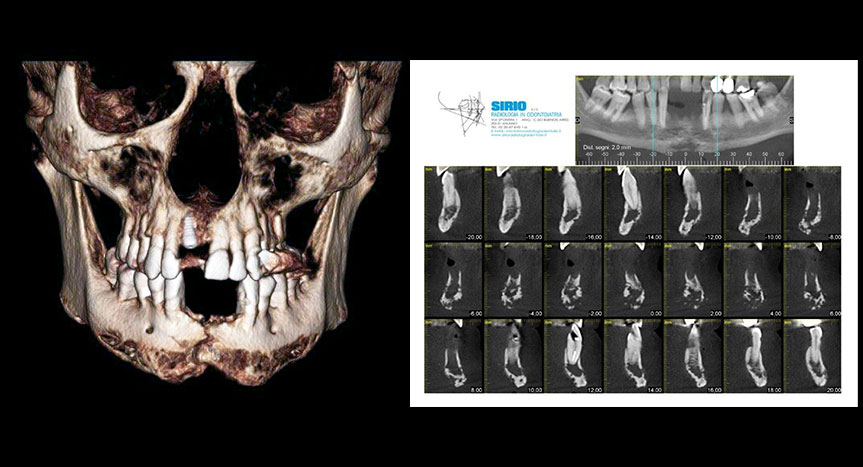

Nell’ambito di questa che viene definita “T-Shape zone”, è possibile sia un inserimento mediano che paramediano. Quest’ultimo è preferibile poiché consente svariati impieghi clinici, ivi compresa l’espansione mascellare, ed al contempo presenta una maggiore sicurezza clinica, essendo più distante dal canale naso-palatino. Tuttavia, l’inserimento paramediano presenta un indice di fallimento lievemente maggiore rispetto a quello mediano, per la maggiore vicinanza alle radici degli incisivi. Sebbene difatti il possibile contatto con le radici non rappresenti un reale rischio di danno per queste ultime (la cui lesione superficiale viene guarita dopo poco con neoapposizione di cemento), dall’altro lato rappresenta un importante fattore di rischio per il fallimento delle TADs. Nella pratica clinica quotidiana, la procedura più comune di inserimento di TADs palatali è quella diretta alla poltrona. In tale flusso di lavoro, definito “inserimento diretto”, l’ortodontista inserisce dapprima le TADs in sede palatina, poi rileva impronte o scansioni necessarie alla costruzione del dispositivo ortodontico. In alcuni casi, in particolar modo in presenza di denti inclusi, dentizione mista o nei casi in cui si ricerchi bicorticalismo, abbiamo la possibilità di utilizzare un protocollo di inserimento “indiretto”, mediante l’ausilio di guide tridimensionali per l’inserimento. In questo flusso di lavoro, l’ortodontista procederà all’inserimento delle TADs mediante la guida di una dima chirurgica, realizzata sulla base dei record diagnostici iniziali del paziente. Quest’ultima può essere pianificata e realizzata semplicemente mediante una sovrapposizione della teleradiografia laterale con una scansione intraorale o impronta della mascella. Diversi studi scientifici hanno validato questa metodica, riportando valori di attendibilità e accuratezza decisamente sufficienti per l’impiego clinico.

Notevole vantaggio di questa metodica di pianificazione (teleradiografia e scansione o impronta) consta nel non dover esporre il paziente ad ulteriori radiazioni, oltre i record convenzionali acquisiti per il convenzionale studio del caso ortodontico. In alternativa, la dima chirurgica può essere progettata anche mediante sovrapposizione di una cbct mascellare con una scansione intraorale o impronta della mascella. Queste due diverse metodiche di pianificazioni e costruzione delle dime di posizionamento non presentano differenze significative in termini di accuratezza, sicurezza e valutazione della dimensione e disponibilità ossea. Naturalmente, è consigliabile l’uso di dime pianificate mediante sovrapposizione con cbct in caso di denti inclusi, dentizione mista o ricerca di bicorticalismo. In tutti gli altri casi, è consigliabile l’impiego di dime realizzate mediante sovrapposizione con la sola teleradiografia laterale, consentendo una significativa riduzione della dose di radiazioni per i pazienti ed al contempo analoga sicurezza in termini di valutazione dell’osso disponibile e di distanza dalle radici. Una volta inserite le TADs si procederà all’applicazione del dispositivo ortodontico desiderato e progettato, che può avvenire in un momento successivo all’inserimento oppure in un momento unico, come introdotto e pubblicato da Maino et al.